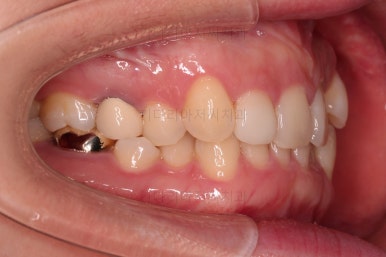

부산치과교정 키다리아저씨치과 초진 시 입안의 모습입니다.

확연히 좌우의 삐뚤어진 정도가 차이나죠.

덧니도 좌측(사진에서 보면 오른쪽) 위아래만 있는 상태고요.

좌측으로 삐뚤어져서 앞니도 좌측으로 쏠려 있는 상태였습니다.